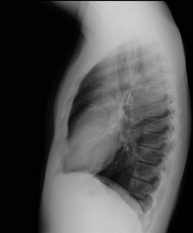

- RX Tórax

Técnica mediante la cual, utilizando rayos X, se obtienen imágenes de la caja torácica (corazón, pulmones, arcos costales, clavículas, etc.) para su estudio. - RX Esternón

- Thoracic spine X-ray

This technique uses X-ray rendered imaging to examine the thoracic spine. Indicated for: trauma, back pain.

- Chest X-ray

A chest X-ray uses a small dose of radiation to obtain a two-dimensional image of the thoracic cavity and its contents (lungs, heart, mediastinum, etc.). It is one of the most commonly performed medical tests.